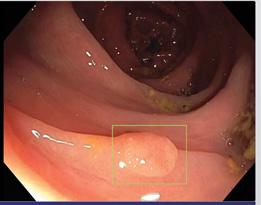

Figur 1. MR- og ultralydbilde av ADPKD nyrer. A) Koronalplan av T2-vektet MR bilde som viser lengde og bredde av nyrene hos en ADPKD pasient. B) Aksialplan av T2-vektet MR bilde av samme pasient hvor også en del levercyster er synlig øverst i bildet. C) Ultralydbilde som viser cyster med tynne septa (hvit på bildet) og væskefylt innhold (svart på bildet). Bruk av MR- og ultralydbilder fra denne pasienten er godkjent av pasienten etter innhentet samtykke (Ø. Eikrem).